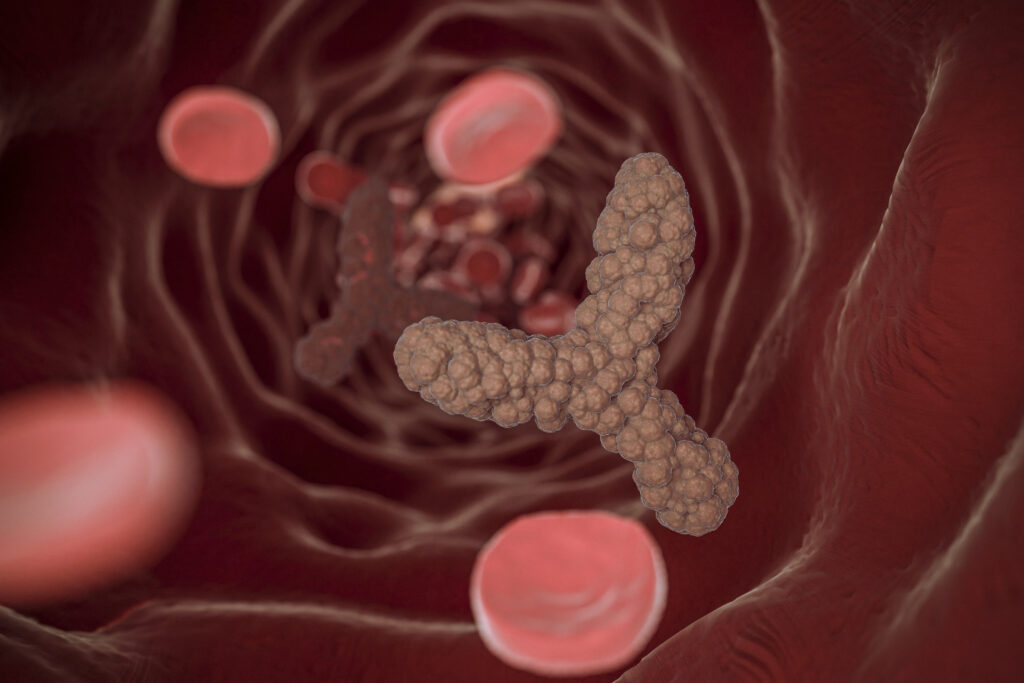

Trombose: o que é, principais sintomas e quando procurar um cirurgião vascular

A trombose é uma condição caracterizada pela formação de um coágulo sanguíneo (trombo) dentro de…